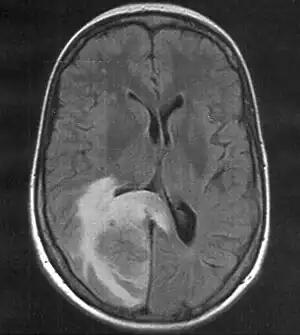

| MRI (T2 flair) showing a brain metastasis with surrouding edema | |